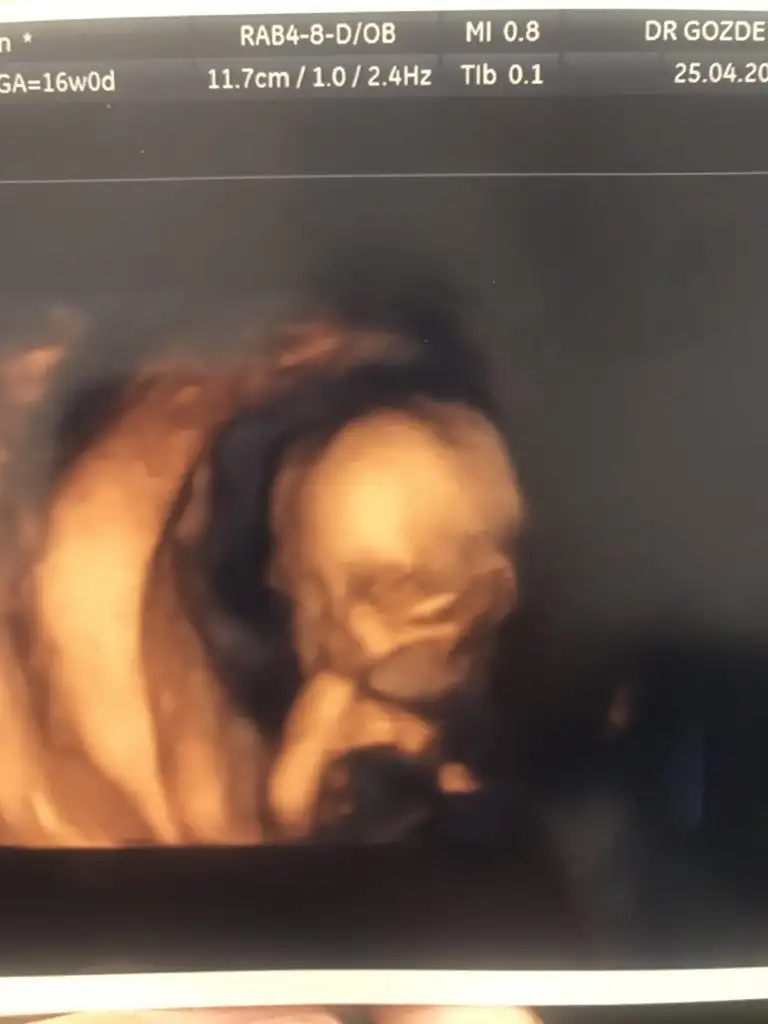

Maşallah yaKızlarrr kızımı gördüm17 cm 195 gram olmuş 1 hafta önde çıktı parmağını emiyordu her şey iyimiş ama akıntıyı önemsemedim alttanda baktı fitil verdi bir de elma sirkesini suya karıştırıp 1,5 lt genital bölgemi yıkamamı söyledi ayrıca bi esans verdi yazarım günde 1 damla iç çamaşırıma damlatıcakmışım

ah kalbim. maşallah allah sağlığını daim etsin.Bu arada doktoruma sordum detaylı için siz mi yapıcaksınız diye evette ben zaten her muayenede onları yapıyorum dedi yarım saat kaldık içerde ben her organına bakıyorum her geldiğinde dedi dakikalarca sanırım özel diede makinası iyi özel bir şey yapmıcam yarım saat bakıcam yine geldiğinde dedi size parmak emen kızımı göstereyimmmm